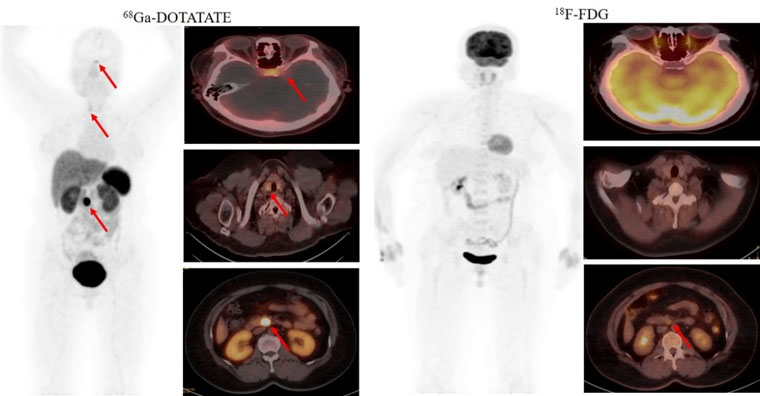

首個病例患者為一名49歲的女性,間斷低血糖超過1年,甲狀旁腺激素檢查異常升高。腦MRI提示為腦垂體微腺瘤,上腹部MRI檢查未發現明顯異常。但臨床懷疑胰腺存在病變,經新探針68Ga-DOTATATE PET/CT檢查,發現了胰腺病灶,綜合診斷多發性內分泌瘤病I型(MEN1型)。經胰腺穿刺病理證實為神經內分泌腫瘤G2。68Ga-DOTATATE及18F-FDG PET/CT雙核素的檢查結果為患者臨床精準診療提供了胰腺病灶的影像學證據。